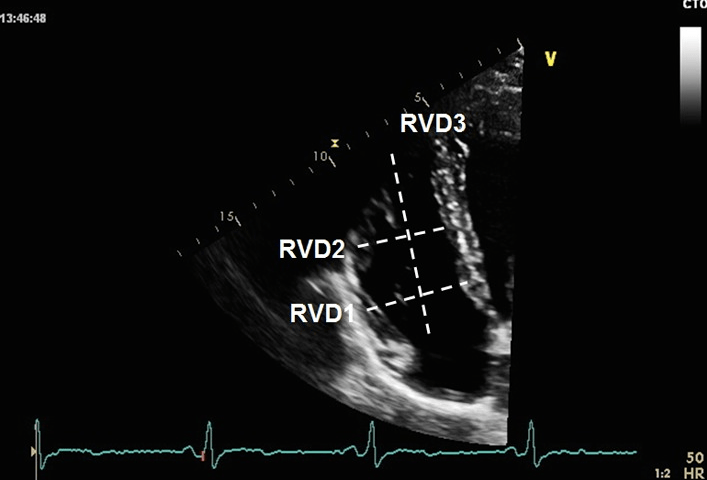

超声心动图评估肺动脉高压准不准?如何评估?_测量_患者_进行